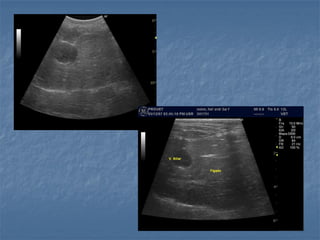

 US é o meio de imagem mais utilizado

para diagnosticar obstrução biliar

extrahepática

 O fígado, trato biliar, pâncreas, intestino

delgado e linfonodos hilares – pesquisa da

etiologia

 Diagnóstico difícil em estágios iniciais

Sinais de Obstrução Biliar

 ducto biliar comum dilatado

- > 0,3 cm para cães

- > 0,5 cm para gatos (excelente indicador!)

 vesícula biliar dilatada (pode ou não estar

presente) – achado inconsistente 

 visibilização de ductos biliares intra-hepáticos